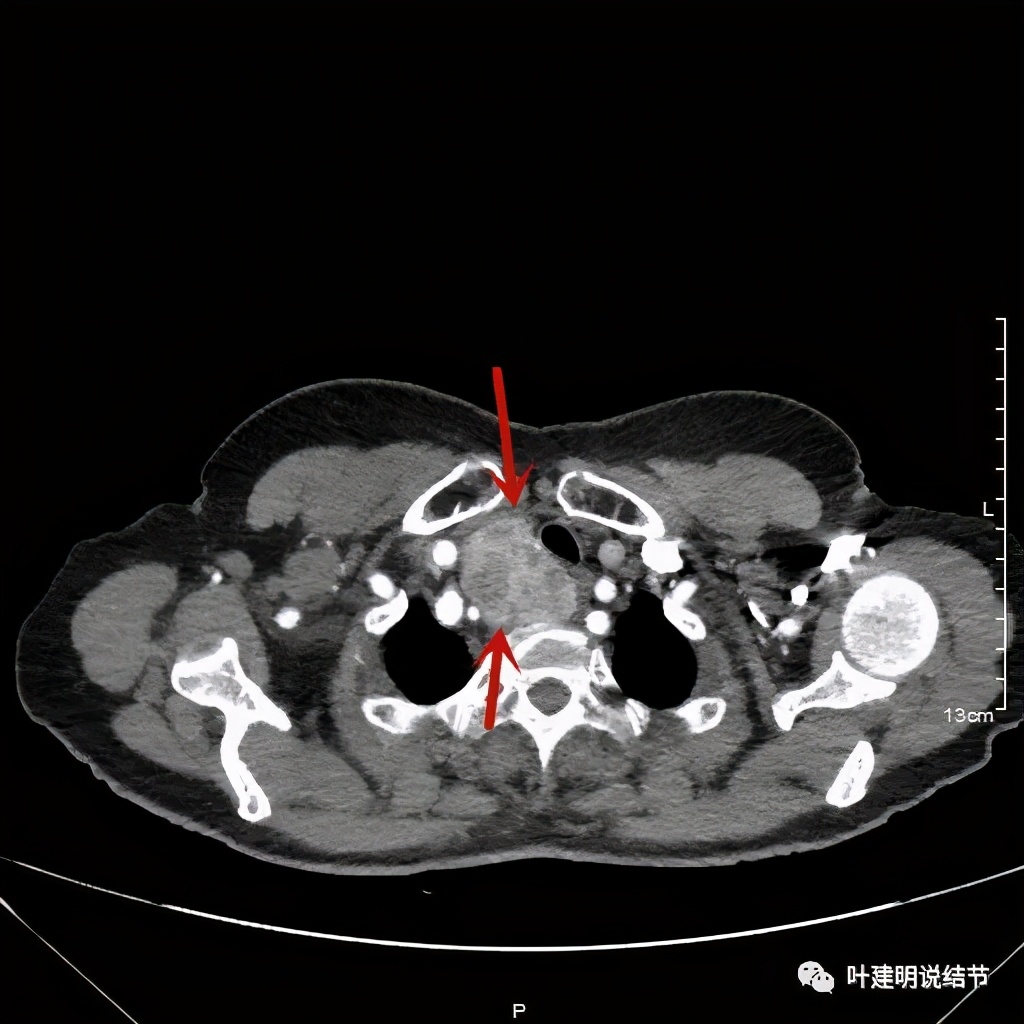

上图红色示肿瘤,黄色示气管,蓝色示上腔静脉

上图红色示肿瘤,黄色示气管,蓝色示上腔静脉,肿瘤已经快要消失了的层面,它距离隆突只有2点几厘米了,位置很低